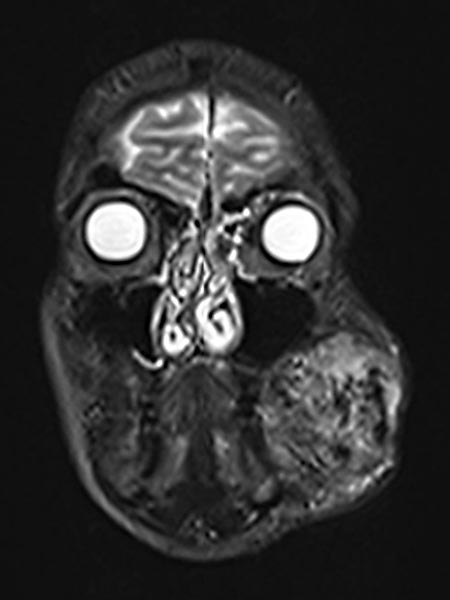

Axial, T2-weighted MRI at the level of the cheek shows the AVM to be relatively hyperintense with edema of the surrounding tissue and extension to the left mandible. In the rostral section some black flow voids are visible as a sign of arteries with fast flow within the AVM.

Coronal fat-suppressed T1-weighted MRI after contrast administration shows the inhomogeneous marked enhancement of the AVM. This is typical of an AVM in the stage of proliferation (corresponding to rapid enlargement) and correlates well with the edema in the T2-weighted images.

Coronal T2-weighted fat-saturated MRI showing hyperintense edema within the AVM and flow voids due to fast-flow arteries.

Inhomogeneous, peripheral enhancement of the proliferating AVM in this axial fat-suppressed T1-weighted MRI after contrast administration. No circumscribed component that is actually solid, unlike in a true vascular tumor.